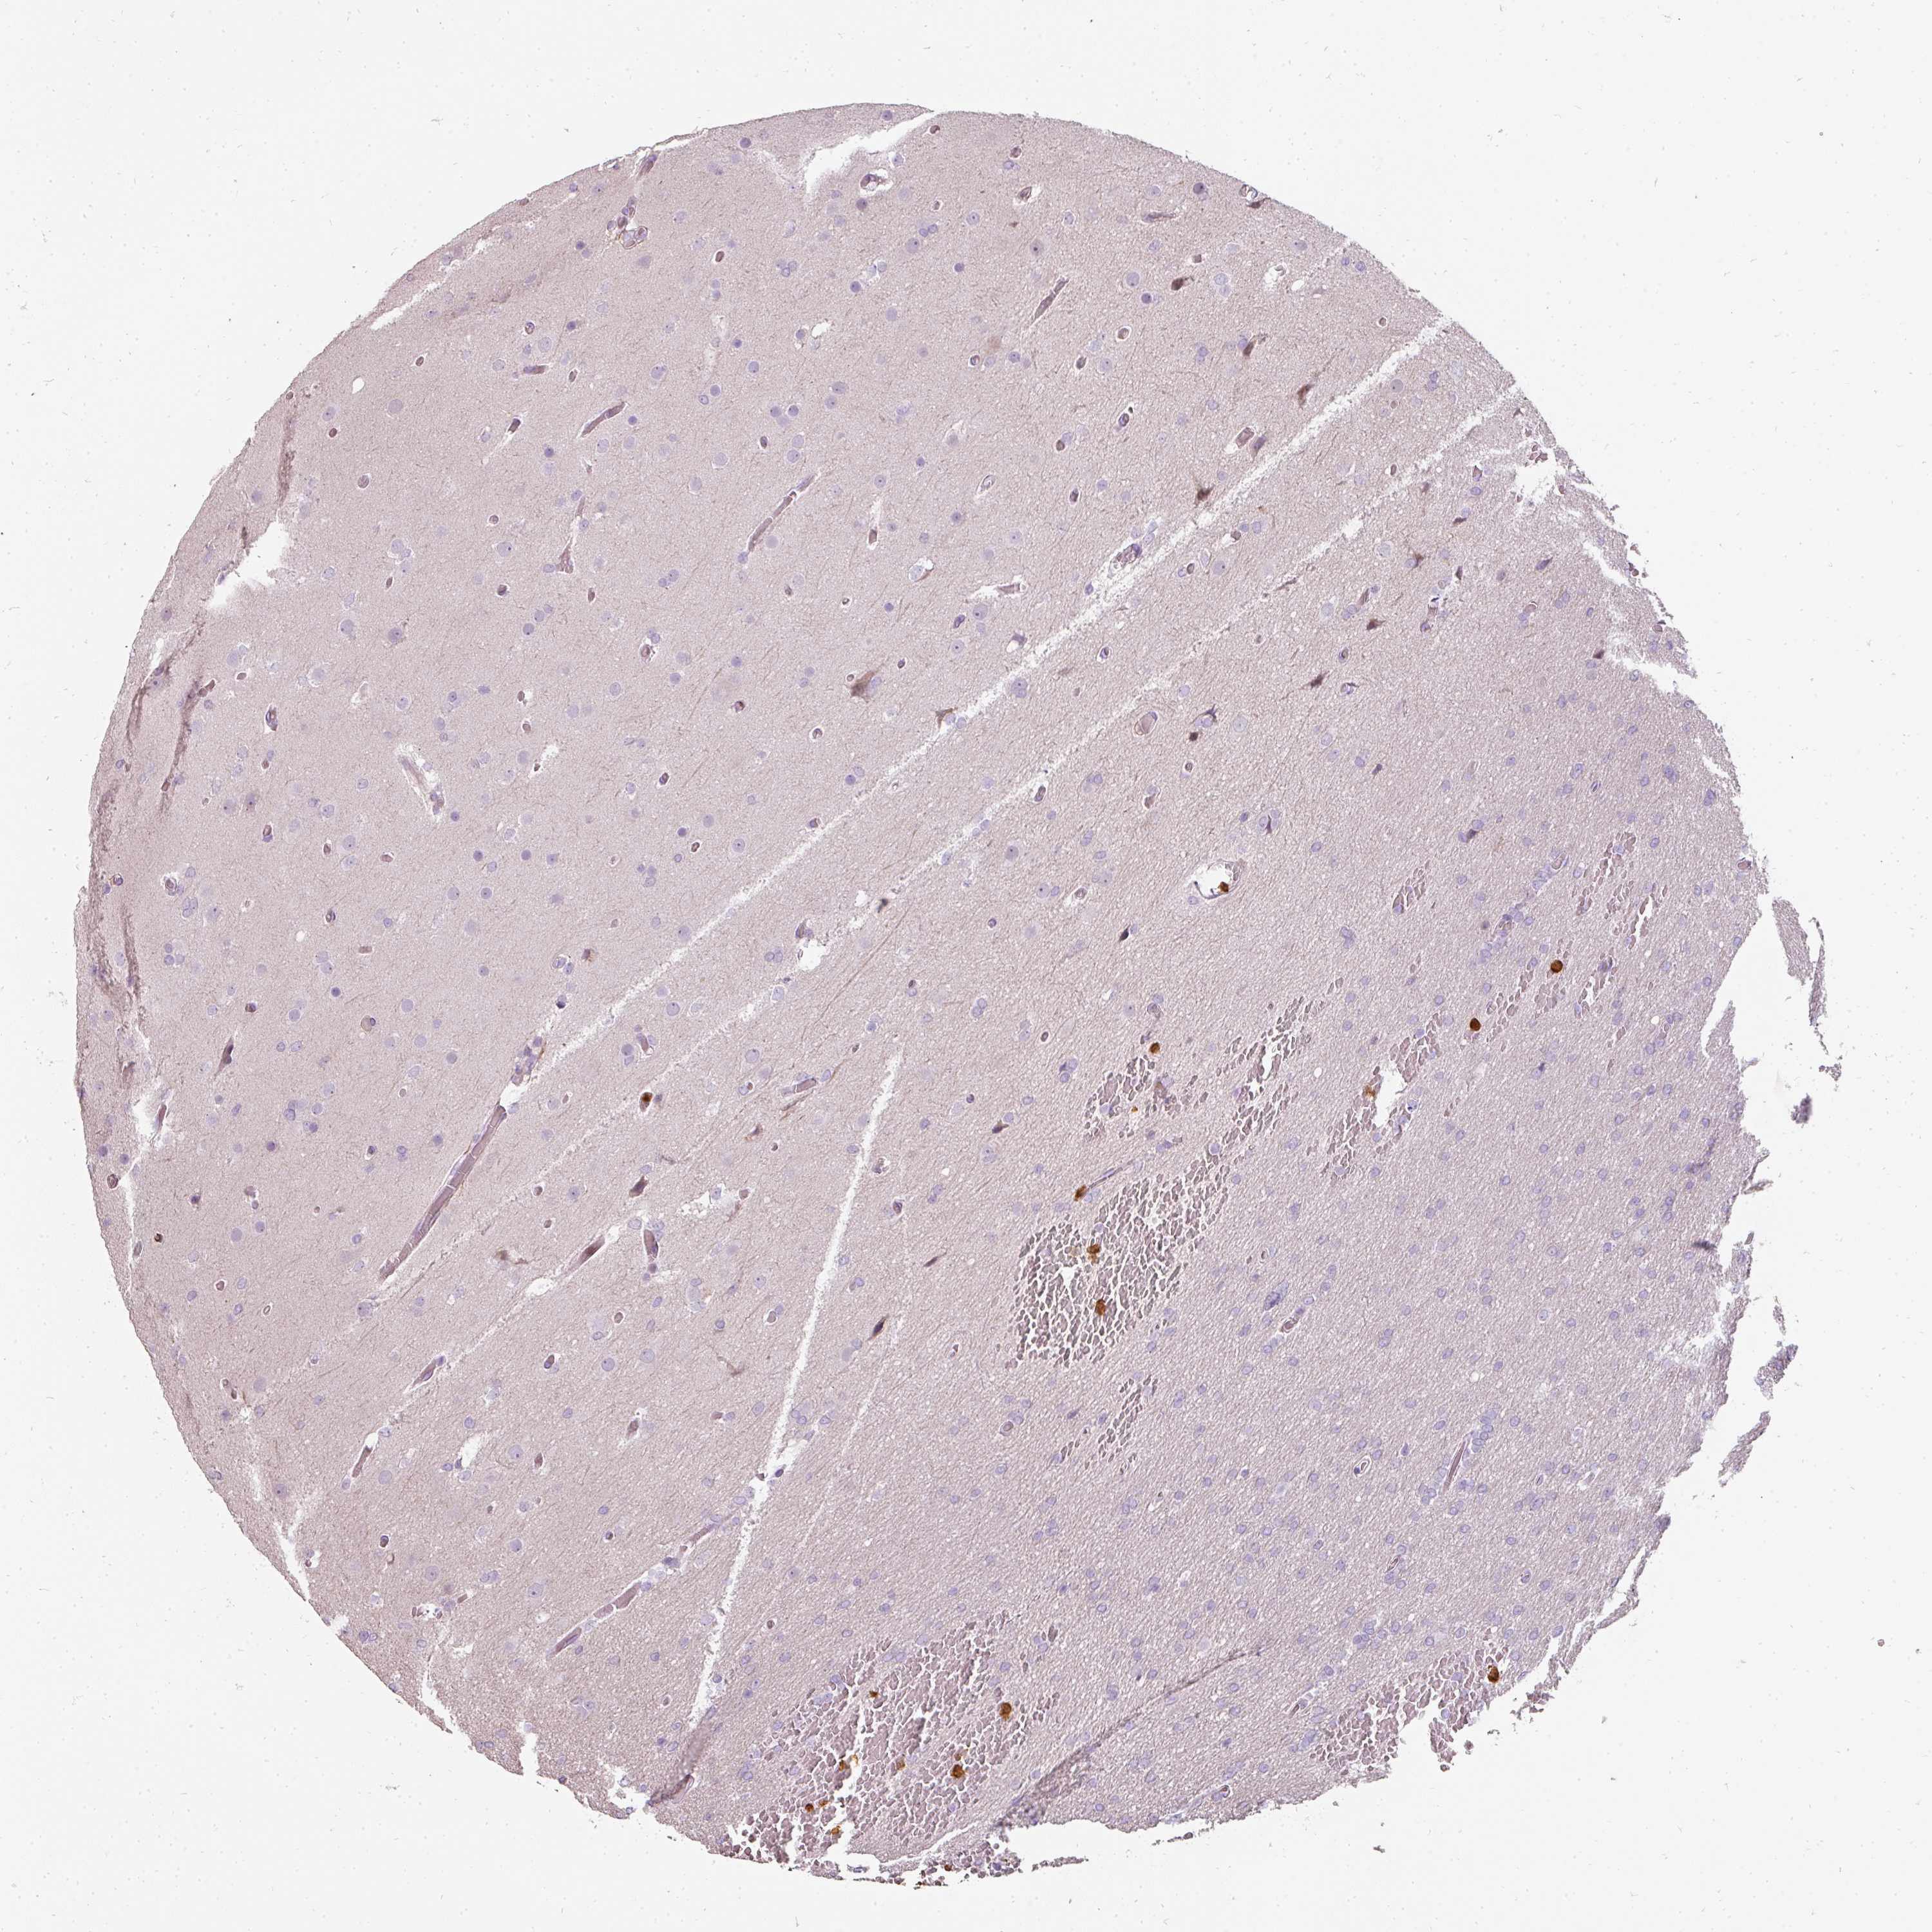

GLIOMA - Protein expressioni

A mouse-over function shows sample information and annotation data. Click on an image to view it in a full screen mode. Samples can be filtered based on level of antibody staining by selecting one or several of the following categories: high, medium, low and not detected. The assay and annotation is described here.

Note that samples used for immunohistochemistry by the Human Protein Atlas do not correspond to samples in the TCGA dataset.

Antibody stainingi

Antibody staining in the annotated cell types in the current human tissue is reported as not detected, low, medium, or high, based on conventional immunohistochemistry profiling in selected tissues. This score is based on the combination of the staining intensity and fraction of stained cells.

Each image is clickable and will lead to virtual microscopy that enables deeper exploration of all samples and also displays staining intensity scores, fraction scores and subcellular localization as well as patient and tissue information for each sample.

Antibody HPA051360

Staining

High

Medium

Low

Not detected

Intensity

Strong

Moderate

Weak

Negative

Quantity

>75%

75%-25%

<25%

None

Location

Nuclear

Cytoplasmic/membranous

Cytoplasmic/membranous,nuclear

Glioma, malignant, High grade

Glioma, malignant, Low grade